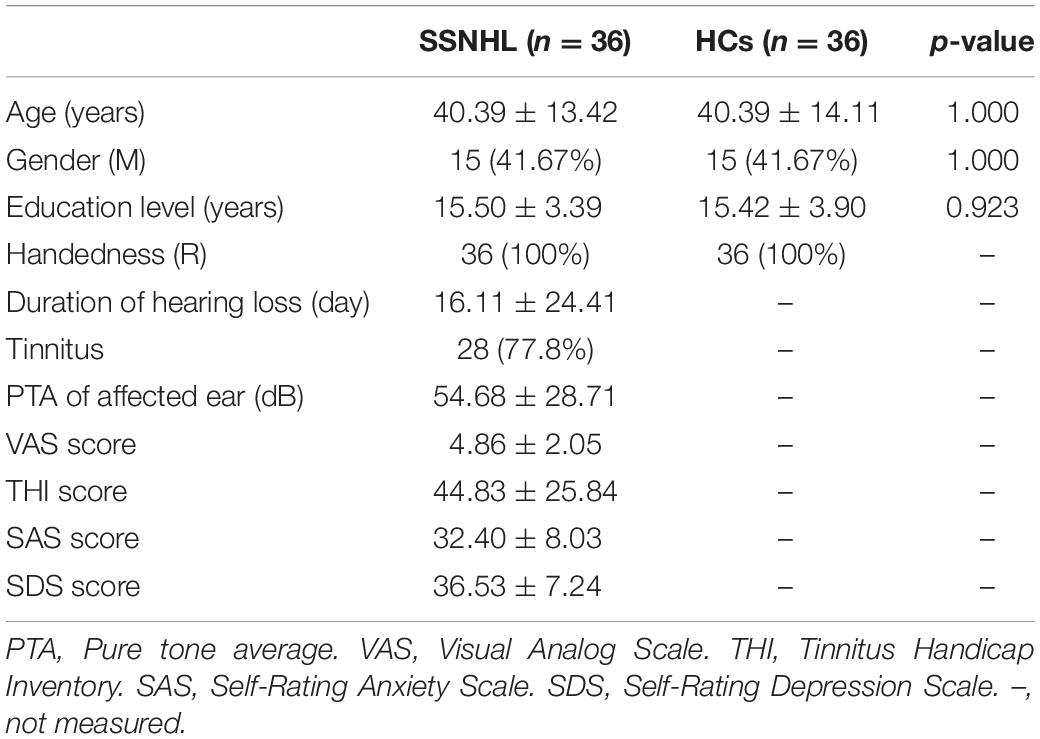

Demographics and clinical characteristic data of all the unilateral SSNHL patients and healthy controls were summarized in Table 1 and Figure 3. No significant differences were found in terms of age, gender, education level.

Figure 3. Average pure tone audiograms for patients with SSNHL averaged over both ears at different frequencies. Data are presented as mean ± SEM. SEM, standard error of mean.